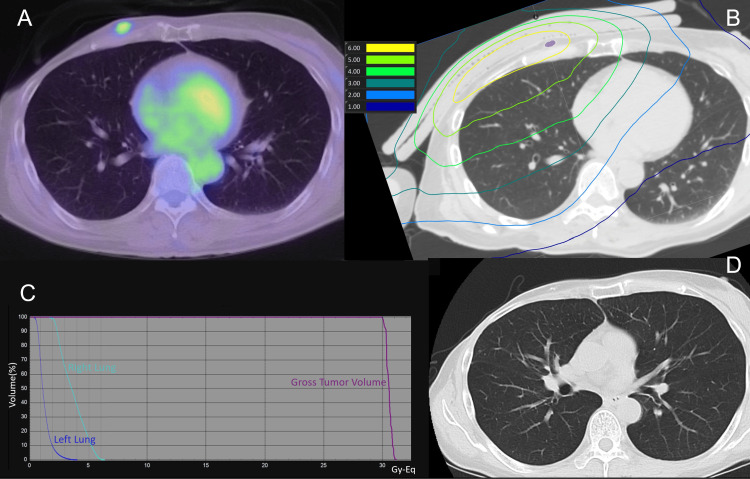

1月21日,日本研究人员发表了硼中子俘获疗法(BNCT)用于放射治疗后复发性高级别脑膜瘤的II 期研究结果。 结果显示:BNCT 组和对照组中 WHO 2 级脑膜瘤患者的中位无进展生存期分别为 15.4和 1.4个月,BNCT组 WHO 3 级脑膜瘤患者的中位无进展生存期为 8.5 个月,而对照组则未确定。BNC...

1月16日,台湾研究人员在《Advances in Radiation Oncology》分享了BNCT复发乳腺癌及脑转移中的应用,4名晚期乳腺癌患者在接受BNCT治疗后肿瘤显著消退,症状明显改善。